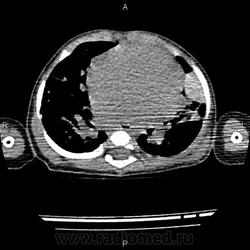

Основной диагноз ВПС: множественные ДМЖП (по типу "Швейцарский сыр"), ДМПП, состояние после оперативного лечения по поводу стеноза легочного ствола. В анамнезе - полисегментарная двустороняя пневмония, сейчас беспокоит кашель. Вопросы возникли по поводу участка уплотнения (V образование? зона консолидации? или еще что-то?) в язычковых сегментах в левом легком.

Обратитесь приватно к Ola-la, а мы почитаем. Не вполне копегаген, но какая-то мозаичная перфузия, ощущение "воздушных ловушек" при бронхиальной обструкции.

законтрастируйте аорту для исключения легочной секвестрации